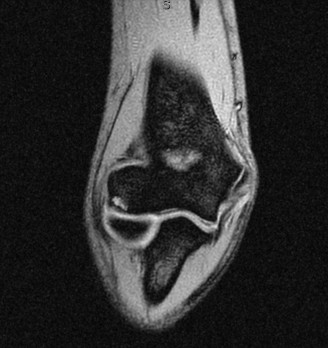

While plain films confirm the presence of osseous reactive changes, Magnetic Resonance Imaging (MRI) is indispensable for evaluating the articular cartilage, the integrity of the UCL, and the presence of occult loose bodies. A high-resolution MRI, preferably an MR Arthrogram (MRA) if subtle UCL pathology is suspected, provides a comprehensive map of the elbow's soft tissue envelope.

In this case, the MRI demonstrates focal chondromalacia and subchondral edema at the posteromedial olecranon tip and the corresponding medial wall of the olecranon fossa—the classic "kissing lesion" of VEO. Crucially, the anterior bundle of the UCL appears continuous and intact, with no evidence of high-grade partial tearing, T-sign (contrast leakage beneath the distal insertion), or severe attenuation. The flexor-pronator mass and the ECRB origin are pristine.